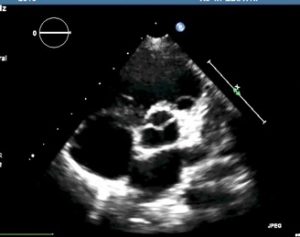

Plano paraesternal corto o transversal

-Posición de la sonda: Para obtener el eje corto o transversal a nivel de los grandes vasos, debemos realizar, partiendo del paraesternal largo una rotación horaria de 90º

-Utilidad: podemos valorar los tractos de entrada y salida del ventrículo derecho; la arteria pulmonar principal, el origen y la zona proximal de ambas ramas; la existencia del ductus arteriosus (por Doppler color, flujo en rojo en rama pulmonar izquierda); la anatomía de la válvula aórtica (” imagen del Mercedes-Benz” y el origen y el trayecto proximal de las arterias coronarias (se precisa experiencia, no incluido en el estudio en la ecocardioscopia).

Si basculamos hacia la punta cardiaca obtendremos un corte a mitad de los ventrículos, pudiendo también valorar los músculos papilares mitrales.